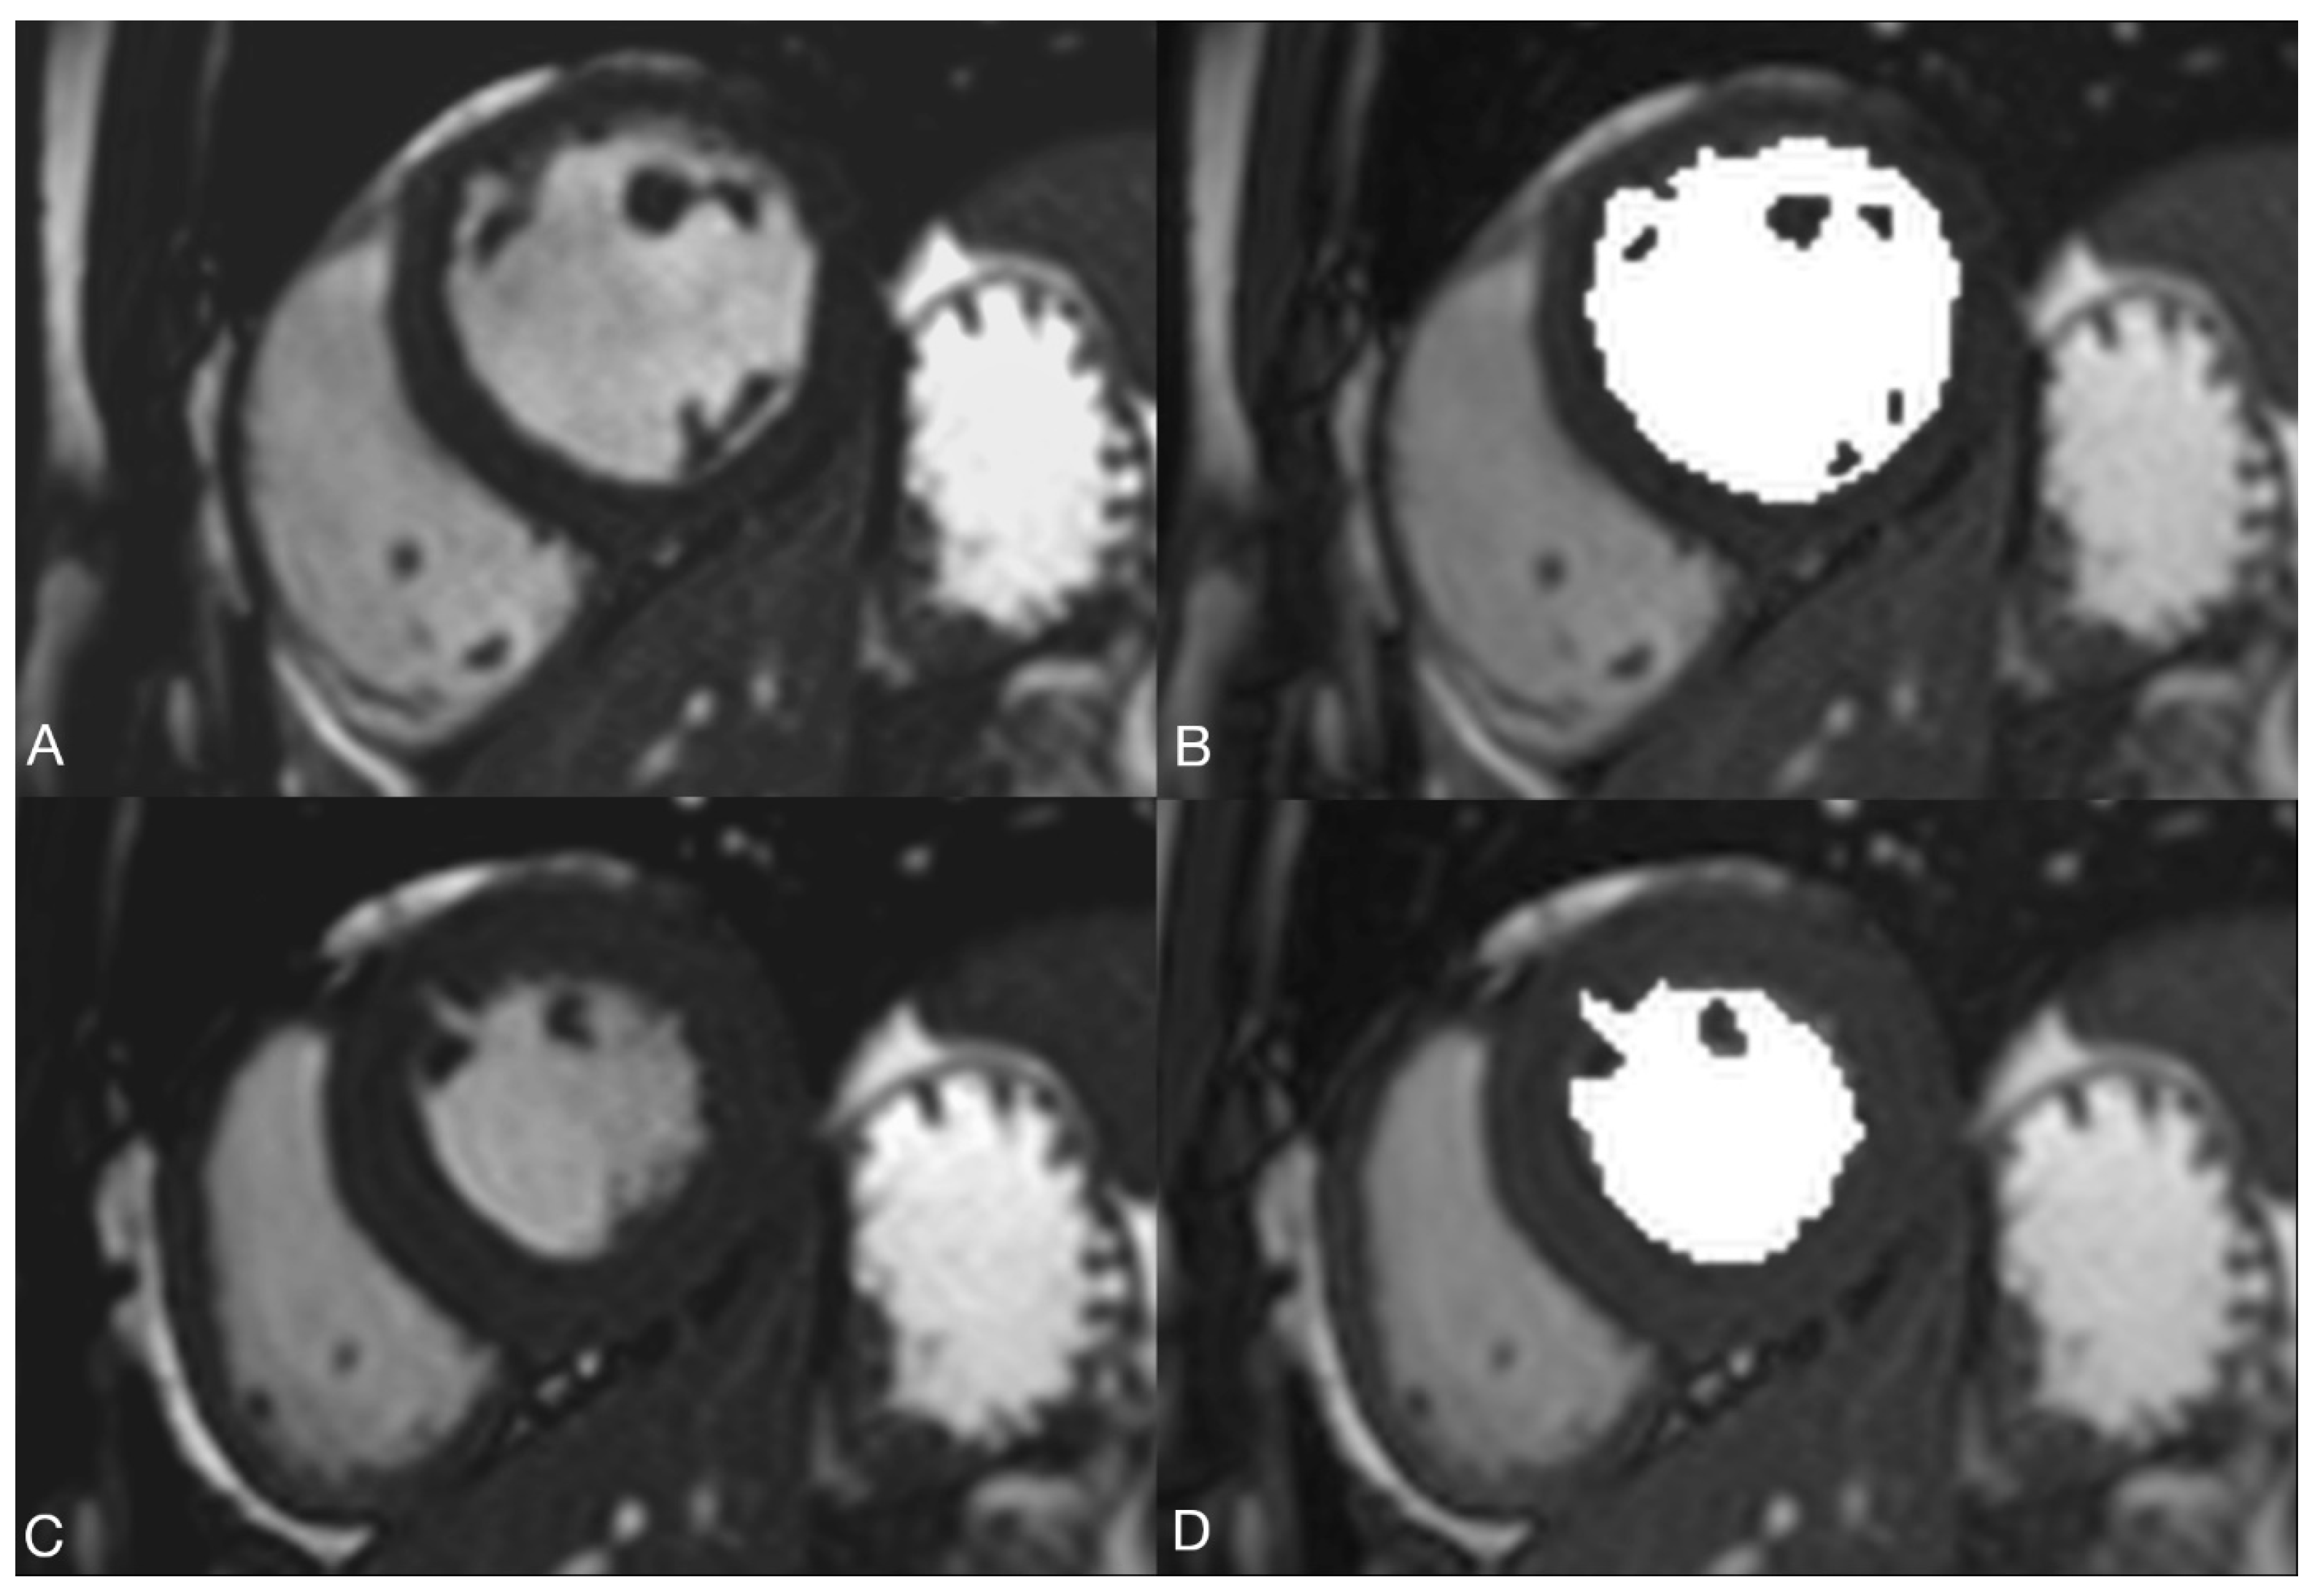

2.2.2. Volume Determination with the Pixel-Based Method (PbM)

2.2.3. Volume Determination According to the Contour Surface Method (=KfM) with SyngoVia